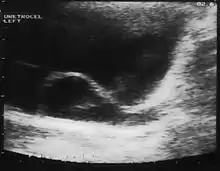

A ureterocele is a congenital abnormality found in the ureter. In this condition the distal ureter balloons at its opening into the bladder, forming a sac-like pouch. It is most often associated with a duplicated collection system, where two ureters drain their respective kidney instead of one. Simple ureterocele, where the condition involves only a single ureter, represents only twenty percent of cases.

Since the advent of the ultrasound, most ureteroceles are diagnosed prenatally. The pediatric and adult conditions are often found incidentally, i.e. through diagnostic imaging performed for unrelated reasons.